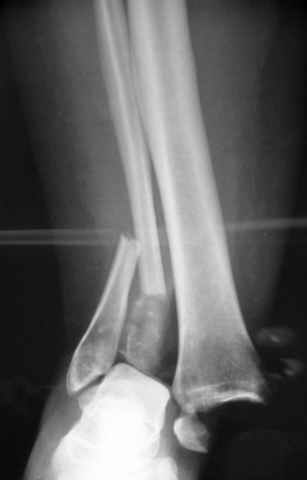

Pilon fracture:

ET> ЕЧ При подобных переломах фиксация малоберцовой кости обеспечивает

ET> низведение латерального тибиального фрагмента - появляется ориентир для

-Появляется ориентир и остов, на чем можно строить восстановление, почему сперва малоберцовую, впервые обьяснили и описали (Pylon type and Ankle fractures) в середине 50х Rienau и Gay.

Восстановливая длину и ротацию малоберцовой кости, затем относительно легче произвести реставрацию остальных элементов перелома дистального эпиметафиза болшеберцовой кости.

конец малоберцевой кости, к нему прикрепляется латеральный суставной фрагмент дистального эпиметафиза большеберцовой кости (как на снимке)

и таранная кость, которые при репозиции малоберцовой кости репонируются автоматически.

-Малоберцовую! Можно низвести аппаратом или пластиной.